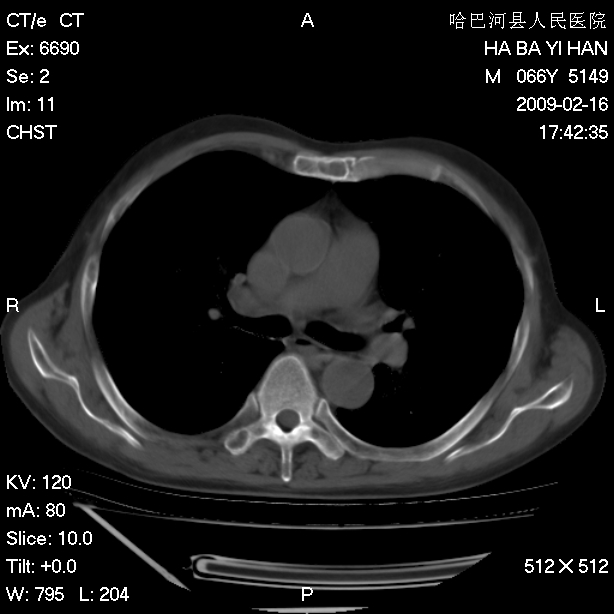

以下是引用huangxun4321在2009-2-16 20:18:00的发言:[br]部分病灶可见硬化边,部分可见骨质破坏消失,部分病灶内可见骨脊,说明病灶内既有良性病变,又有恶性病变,考虑骨巨细胞瘤恶变,未除骨纤恶变,畸形性骨炎少见,亦要考虑.

以下是引用731208在2009-2-16 20:31:00的发言:[br]考虑恶性胸膜间皮瘤并肋骨,脊柱转移。

以下是引用yijiansheng在2009-2-16 20:16:00的发言:[br]考虑恶性胸膜间皮瘤并肋骨,脊柱转移。

以下是引用形影不离在2009-2-16 19:55:00的发言:[br]考虑多发性转移瘤。